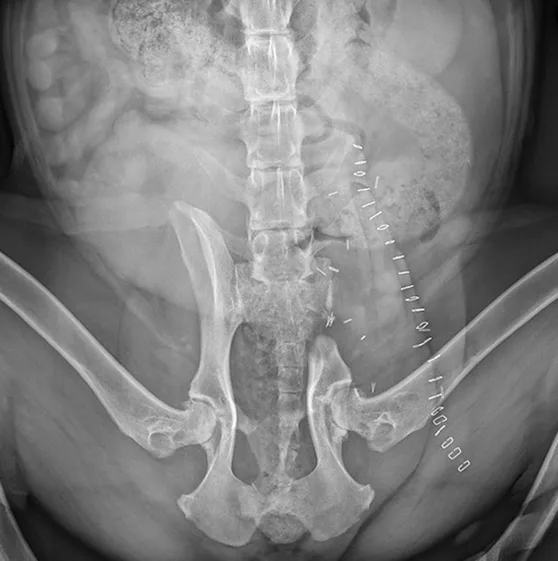

FIGURE 2

Axial CT images showing a large mass arising from the right ilium with a significant soft-tissue component in both the inner and outer tables of the pelvis

Because the lungs are the most common site of metastasis in cases of chondrosarcoma, staging was determined via bone scan and chest CT, which confirmed that there were no other sites of disease. Staging was determined to be Enneking Stage IB; prognosis was good overall. Core needle biopsy confirmed low-grade chondrosarcoma.